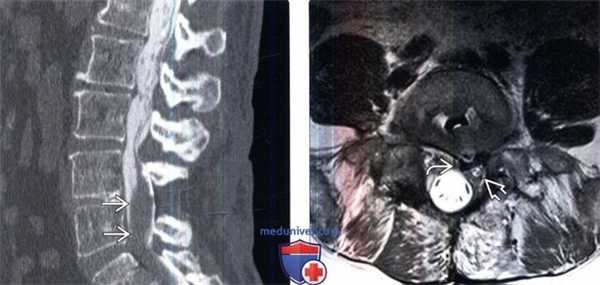

(Слева) Сагиттальный КТ-срез с КУ: после миелографии определяется крупный дефект наполнения мягкотканной плотности, сливающийся с корешками конского хвоста и представляющий собой хроническую воспалительную псевдоопухоль при арахноидите.

(Справа) Аксиальный срез, Т2-ВИ: неправильное расположение межтелового кейджа на уровне L4-L5, задний край кейджа касается края твердой мозговой оболочки и левого корешка S1.